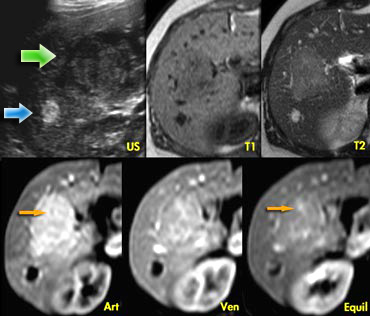

Hemangioma and FNH on ultrasound and dynamic MR. Hemangioma and FNH on ultrasound and dynamic MR.

Focal Nodular Hyperplasia (4)

The ultrasound image on the left shows two lesions.

The small one (blue arrow) is characteristic of a hemangioma, while the larger one (green arrow) is non specific on US.

On T2WI the hemangioma shows the typical homogeneous hyperintensity .

The larger lesion is somewhat hypointense on T1 and somewhat hyperintense on T2.

The enhancement is almost homogeneous with small septae that do not enhance in the arterial phase and do show late enhancement (yellow arrows).

The enhancement is almost homogeneous with small septae that do not enhance in the arterial phase, and do show late enhancement (yellow arrows).

We also characterize this lesion as FNH.